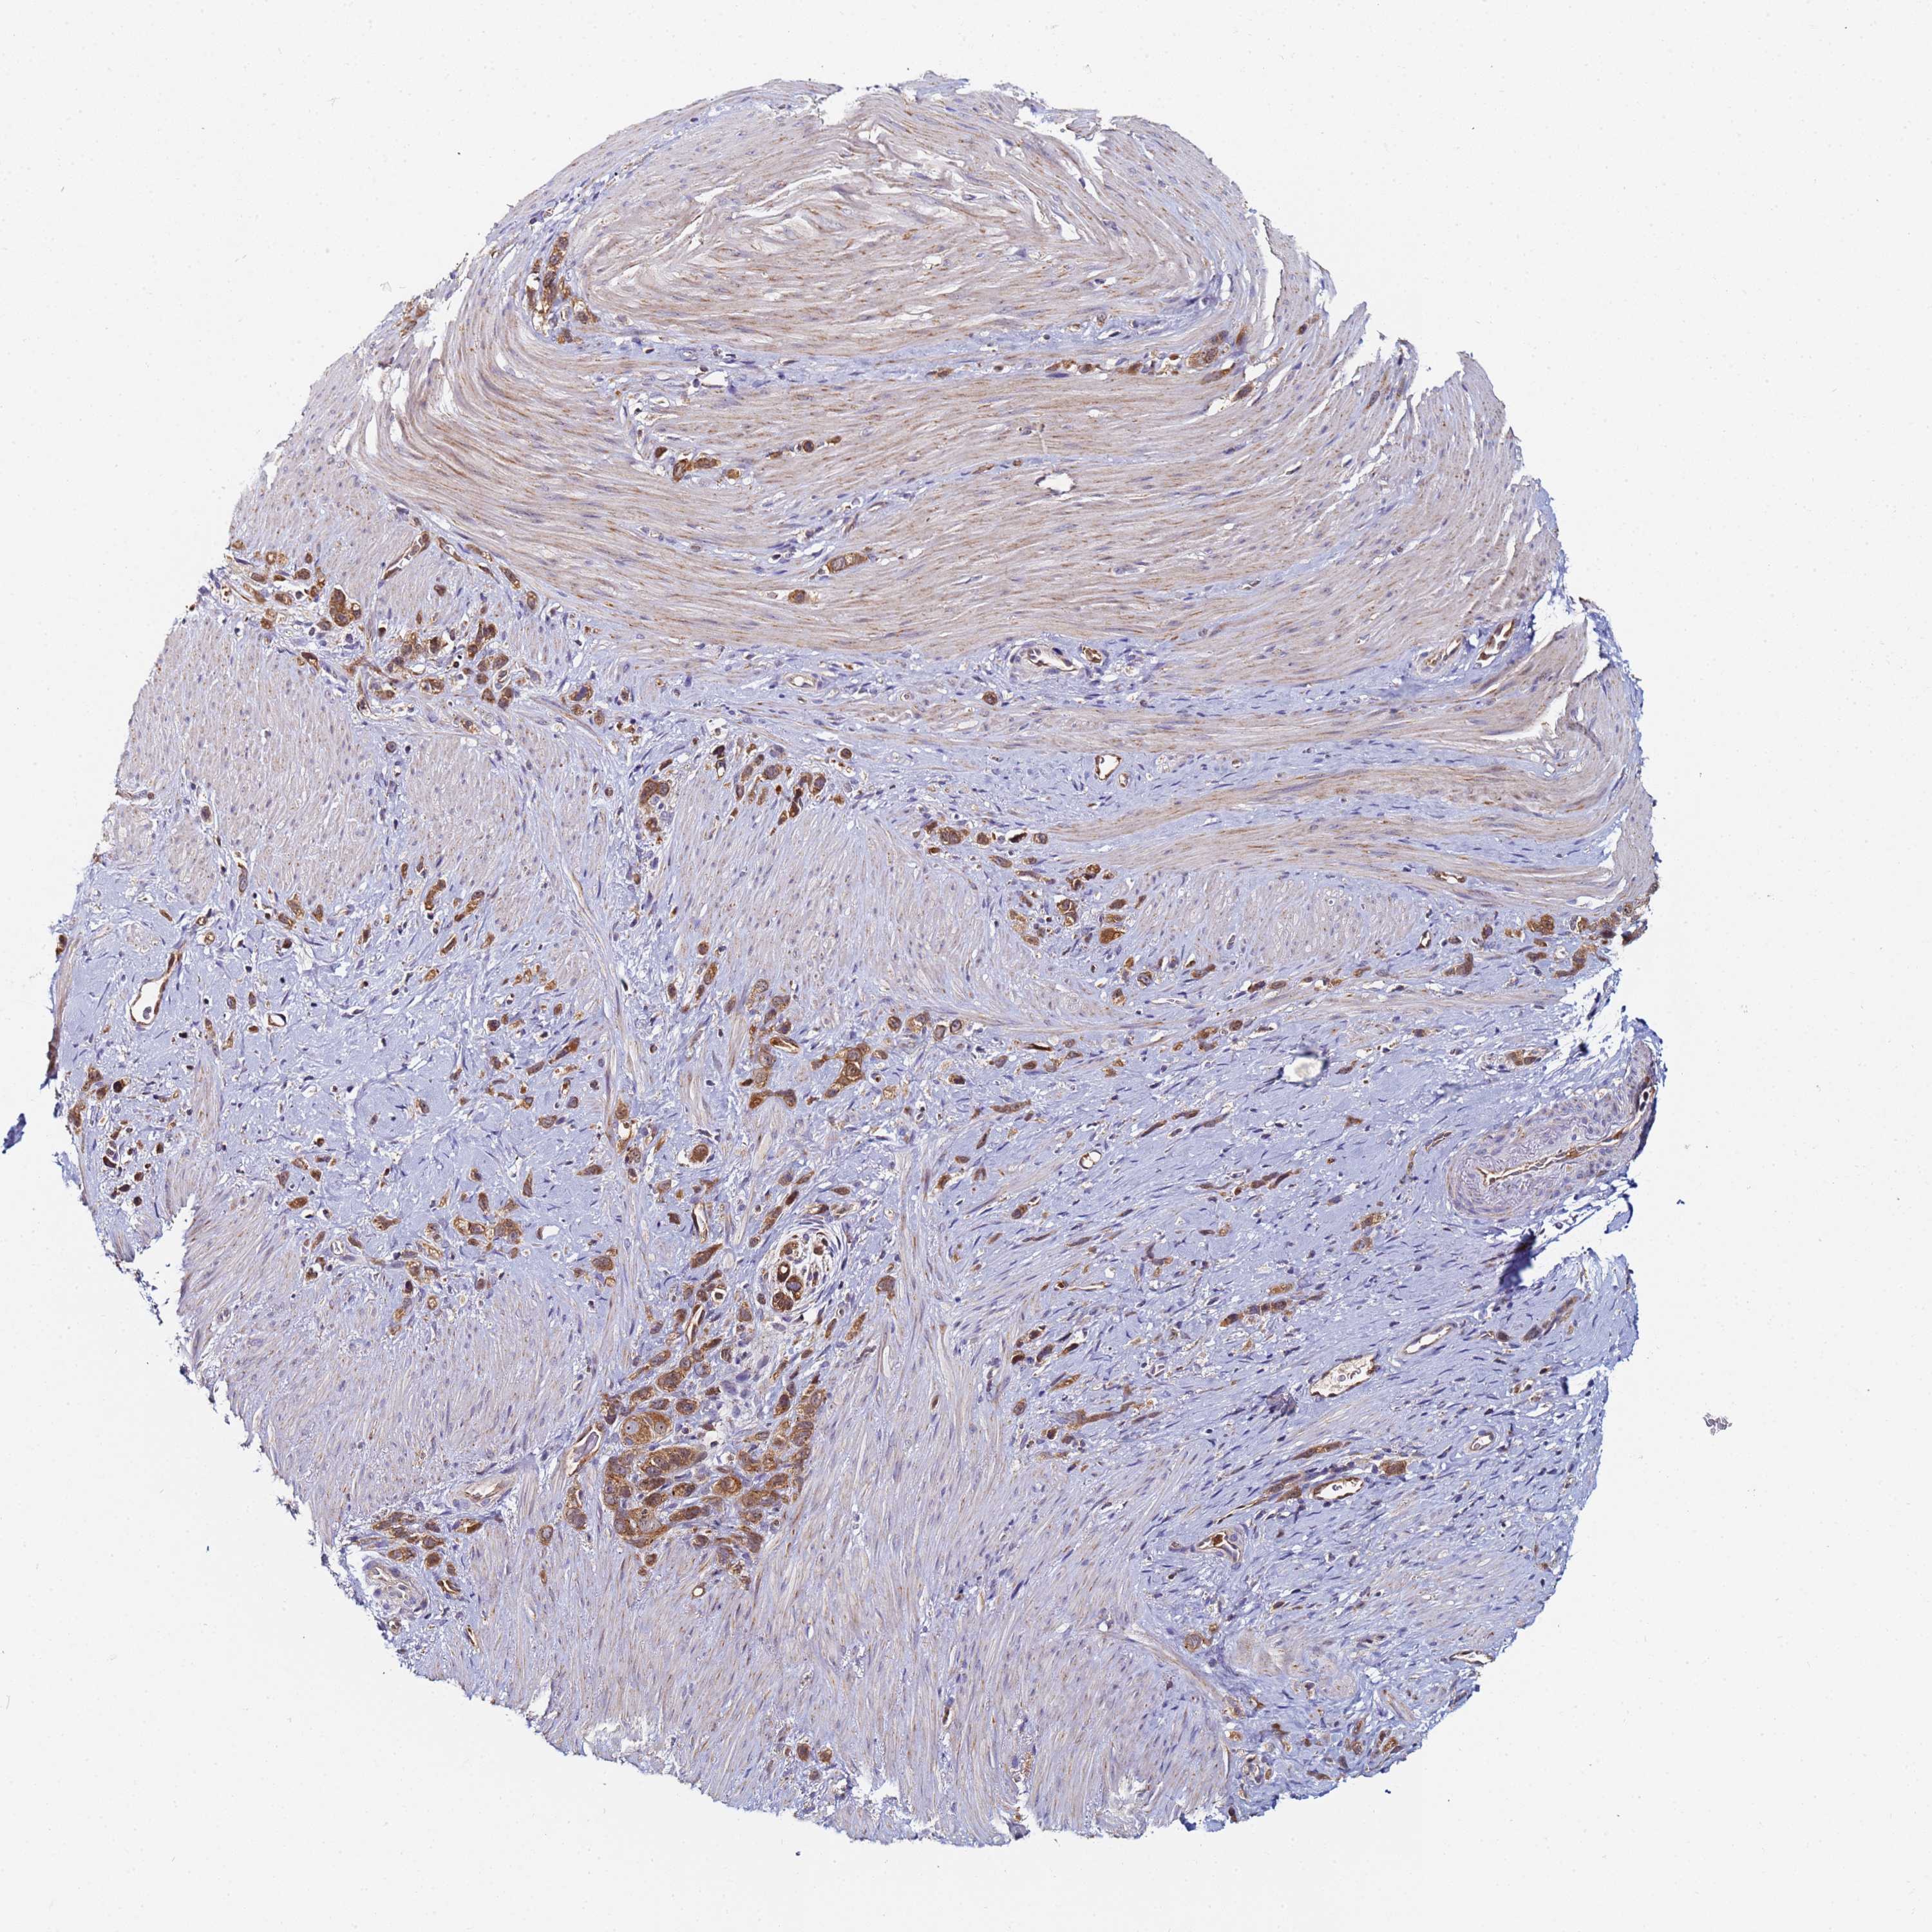

STOMACH CANCER - Protein expressioni

A mouse-over function shows sample information and annotation data. Click on an image to view it in a full screen mode. Samples can be filtered based on level of antibody staining by selecting one or several of the following categories: high, medium, low and not detected. The assay and annotation is described here.

Note that samples used for immunohistochemistry by the Human Protein Atlas do not correspond to samples in the TCGA dataset.

Antibody stainingi

Antibody staining in the annotated cell types in the current human tissue is reported as not detected, low, medium, or high, based on conventional immunohistochemistry profiling in selected tissues. This score is based on the combination of the staining intensity and fraction of stained cells.

Each image is clickable and will lead to virtual microscopy that enables deeper exploration of all samples and also displays staining intensity scores, fraction scores and subcellular localization as well as patient and tissue information for each sample.

Antibody HPA045052

Staining

High

Medium

Low

Not detected

Intensity

Strong

Moderate

Weak

Negative

Quantity

>75%

75%-25%

<25%

None

Location

Nuclear

Cytoplasmic/membranous

Cytoplasmic/membranous,nuclear

Adenocarcinoma, NOS